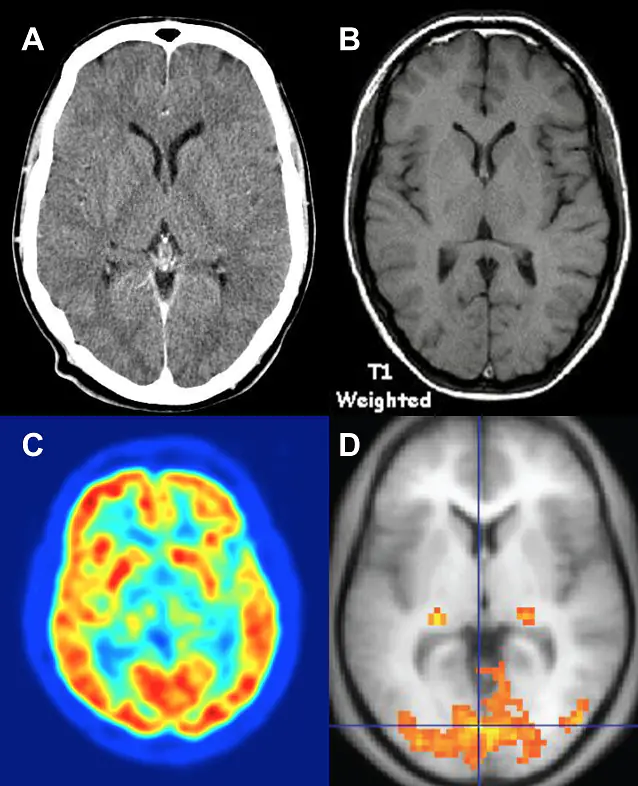

Utilizing MRI, fMRI, PET, CT, and other brain scans to aid in the diagnosis and treatment of mental health conditions.

Additionally, treatment teams can conduct cognitive assessments to see where patients lie on activities of daily living and prescribe medication/accommodations to address these issues.

Thorough neurological assessments can troubleshoot the process of finding the best medication, supplements, and action plan for overcoming a mental health setback.